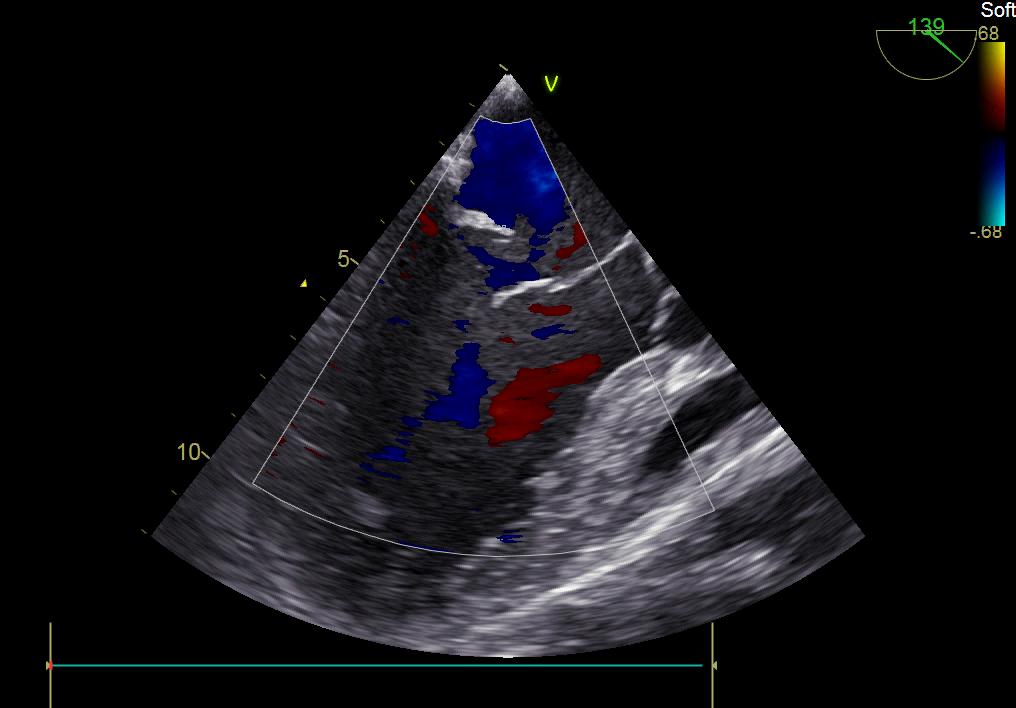

患者何某,42歲男性,因心功能不全入住我院心胸外科,心臟彩超提示二尖瓣后葉脫垂伴有重度返流及心臟擴(kuò)大,在迅速糾正心衰后,手術(shù)便提上日程,心胸外科廖金文主任多次組織全科及兄弟科室討論,在二尖瓣置換及成形術(shù)上,最終決定采取二尖瓣成形術(shù)。為保證手術(shù)安全,討論圍手術(shù)期各個(gè)細(xì)節(jié),所謂細(xì)節(jié)決定成敗,因?yàn)樾g(shù)前的細(xì)致全面,加上術(shù)中的一絲不茍及術(shù)后的精細(xì)化管理,患者術(shù)后恢復(fù)順利,健康出院,復(fù)查心臟彩超未見二尖瓣返流。

術(shù)前彩超